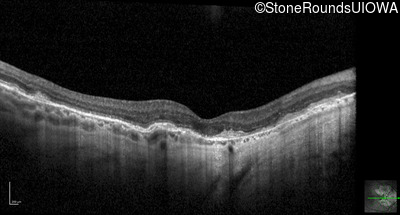

Optical Coherence Tomography - Left - 20/20 -2

Exemplar / OCT Stack

OCT Stack